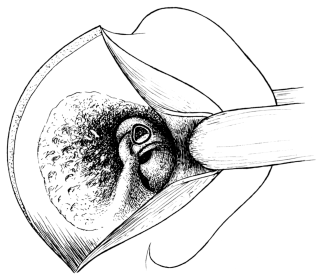

| 41. | Sims’s Operation for the Repair of a Vesico-vaginal Fistula | 136 |

| 42. | Simon’s Operation for the Repair of a Vesico-vaginal Fistula | 136 |